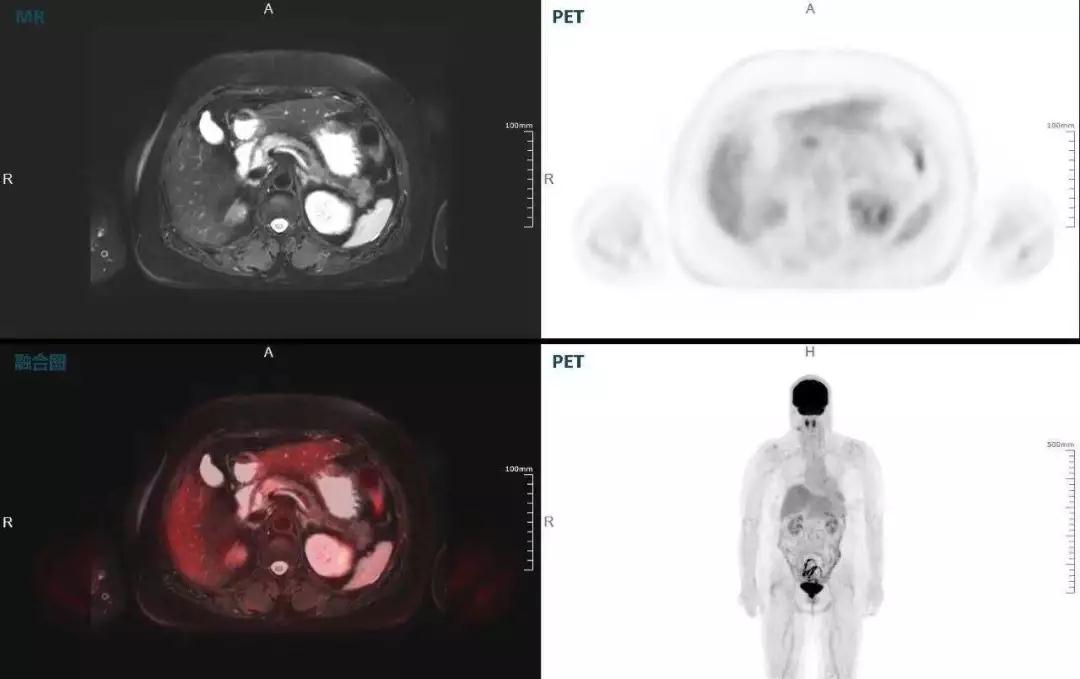

肝癌

聯(lián)影“時空一體”超清TOF PET/MR搭載的壓縮感知技術(shù),能夠同時實現(xiàn)16期成像,精準(zhǔn)捕獲肝臟動態(tài)影像的每一瞬間,同時兼顧早期與晚期等全部期相的完整病灶信息,實時、全方位鎖定病灶。同時,基于其2.8mm超高分辨率,能夠精細(xì)呈現(xiàn)腫瘤邊界信息,捕捉局部微小病灶與遠(yuǎn)端轉(zhuǎn)移灶,助力醫(yī)生精準(zhǔn)診斷。

(對于同一例肝臟惡性腫瘤,PET-CT與PET/MR成像對比。可以看到,聯(lián)影PET/MR圖像對腫瘤邊界和FDG高濃聚區(qū)域清晰顯示。)